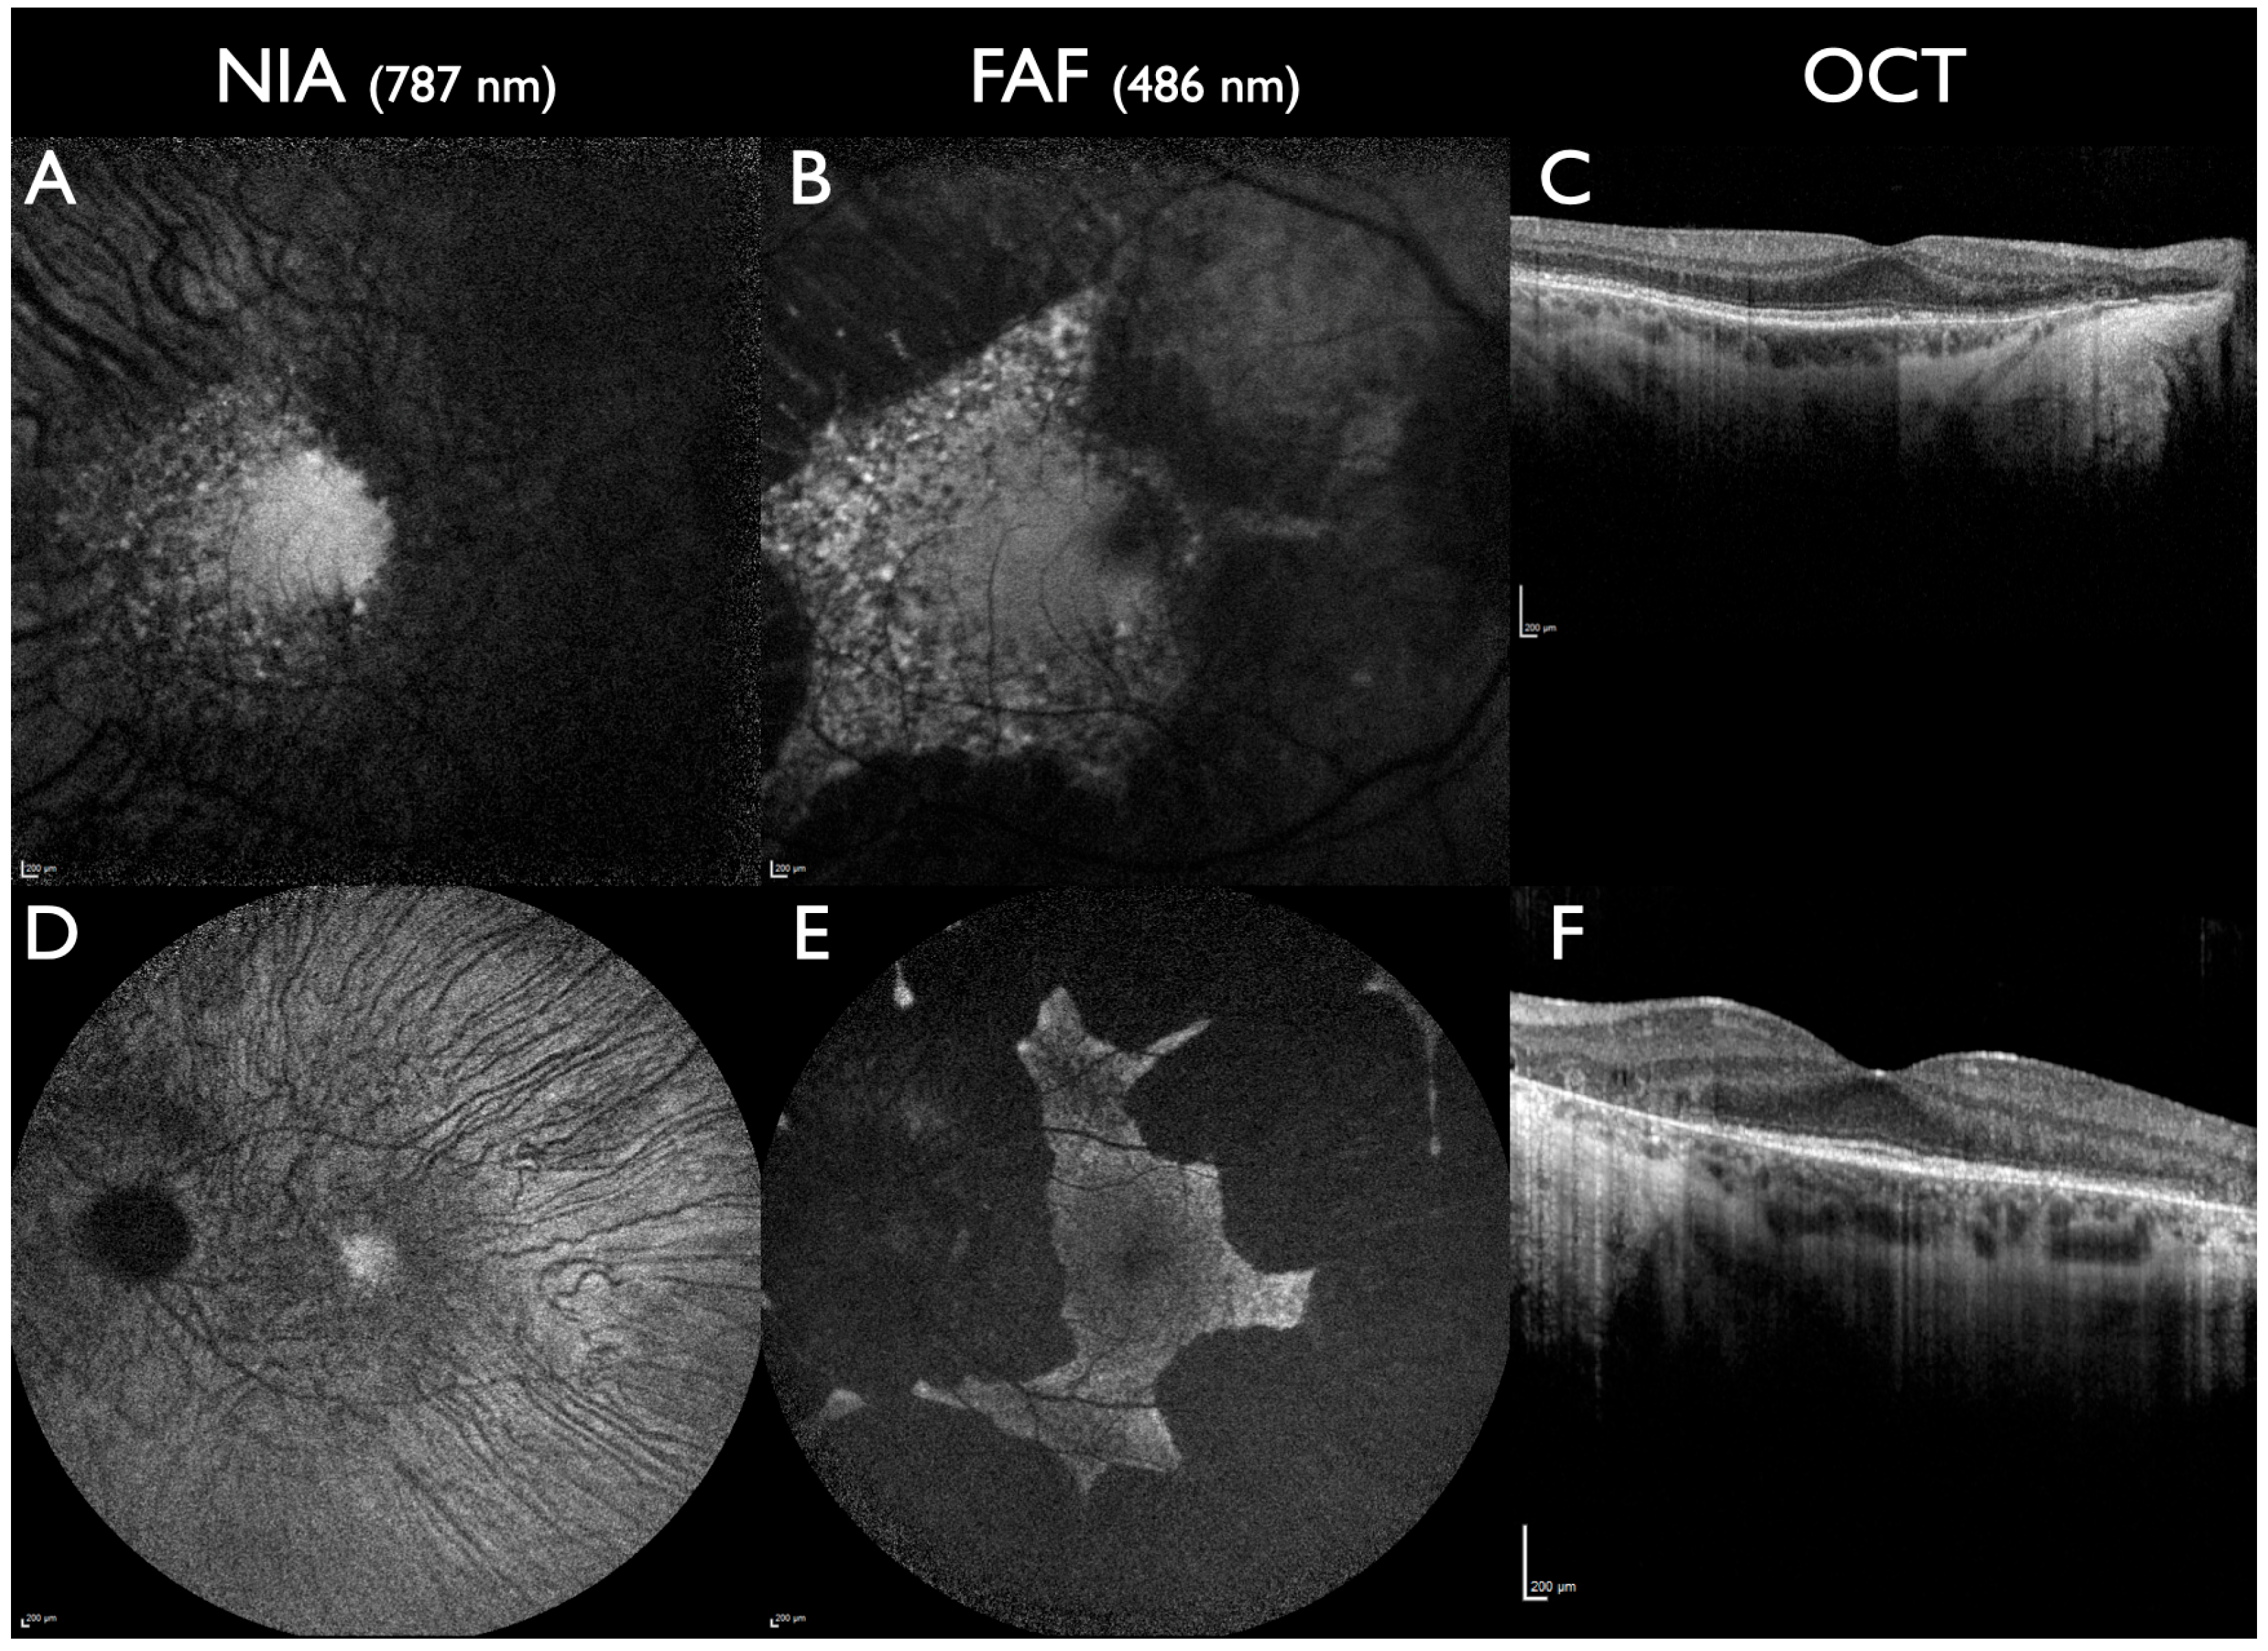

| ABCA4-associated disorders | -Variable: multiple fleck-like lesions or central lesions surrounded by a ring of increased intensity -Marked reduction in intensity in progressed stages -Peripapillary sparing -Subfoveal intensity loss associated with reduced VA [56,57] | -Variable: multiple fleck-like lesions or central lesions surrounded by a ring of increased intensity -Peripapillary sparing | -Subretinal deposits -Loss of outer retinal layers (EZ line) and RPE | -NIA alterations precede FAF alterations: -Affected area with NIA larger compared to FAF and OCT [49,50,51] -Area of reduced intensity larger than EZ loss in OCT [52,53,54,55] |

| Macular dystrophies | Variable: multiple fleck-like lesions or central lesions surrounded by a ring of increased intensity | Variable: multiple fleck-like lesions or central lesions surrounded by a ring of increased intensity | -Subretinal deposits -Loss of retinal outer retinal layers (EZ line) and RPE | -Lesion area larger compared to FAF in MD associated with ABCC6, PROM1, and PRPH2 [41,66,68] -NIA intensity reduction as earliest sign in PRPH2 compared to FAF/OCT [67] |

| Cone-rod dystrophies | -Variable: multiple fleck-like lesions or pericentral ring of increased intensity with centrally reduced intensity -Reduced intensity in foveal cavitation | Variable: multiple fleck-like lesions or pericentral ring of increased intensity with centrally reduced intensity | Variable: subretinal deposits, loss of outer retinal layers (EZ line) and RPE, foveal cavitation in some cases | -Loss of NIA intensity more wide-spread compared to FAF [68,69,70,71,72,73] -In foveal cavitation, NIA intensity loss is larger compared to OCT EZ line loss [74] |